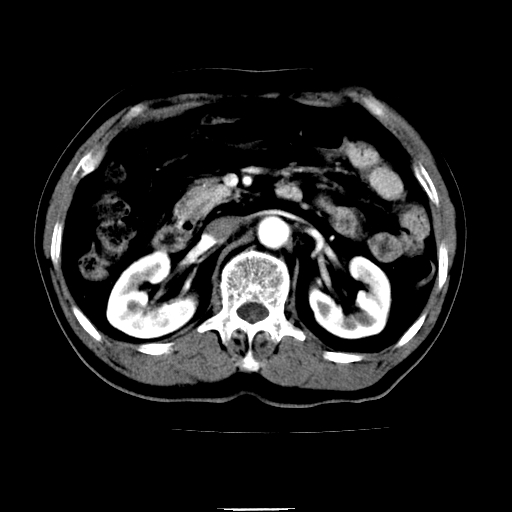

以下是引用chenqiong在2010-3-25 20:56:00的发言:[br]1、胆囊炎,胆囊息肉[br]2、肝内胆管及胆总管扩张,胆总管下端结石[br]3、十二指肠乳头旁憩室

以下是引用zxl51642在2010-3-26 10:47:00的发言:[br]胆囊炎,胆囊息肉,胆总管扩张,但未看到明显肿块,肝内胆管扩张不像恶性,炎性狭窄或阴性结石可能吧,建议mrcp,右肾小囊肿